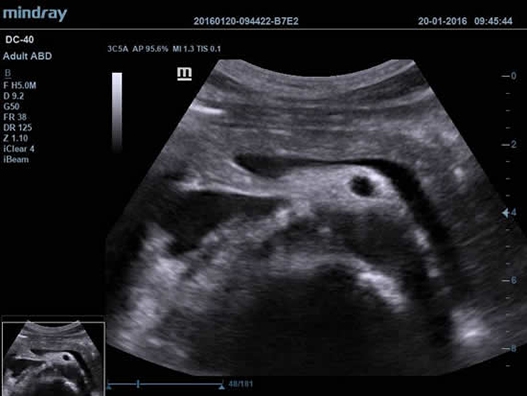

Mindray DC-40 - передовая УЗ-станция с выдающимися возможностями в области медицинской диагностики. Компания Mindray разработала это устройство с учетом высоких требований врачей к качеству изображения и быстродействию. DC-40 обеспечивает высокое качество изображения и точность диагностики, что является необходимым в повседневной практике врачей. Технологии, применяемые в этом устройстве, позволяют получать четкое и детализированное изображение.

Технологии iBeam, iClear и iScape, применяемые в DC-40, позволяют получать объемные изображения высокого качества без помех и зернистости в зоне сигнала. Панорамная визуализация с расширенным обзором анатомических структур решает проблемы сложных диагнозов, которые ранее создавали значительные трудности в ультразвуковой диагностике.

УЗИ-аппарат DC-40 - это передовое медицинское оборудование, которое на протяжении многих лет поможет решать проблемы ваших пациентов, предоставляя готовые и точные диагнозы, выявляя даже самые серьезные патологии на ранних стадиях развития.